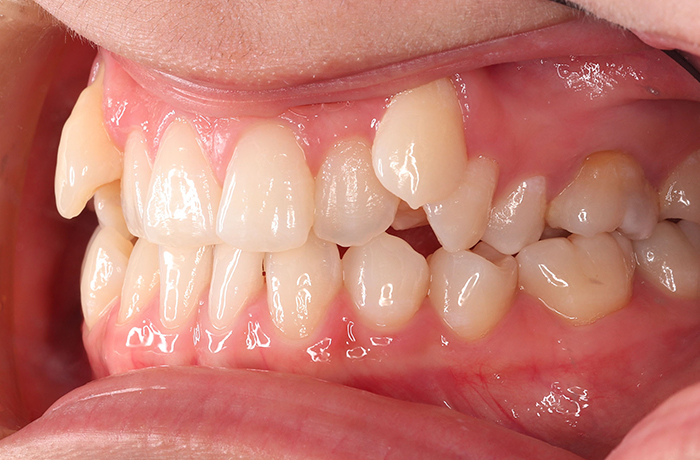

A様

治療前

before

年齢 31歳

性別 女性

治療名称 マウスピース型カスタムメイド矯正歯科装置(インビザライン)・コンプリヘンシブパッケージ(難症例)

総額治療費用 935,000円(税込10%) 金額備考 精密検査料・診断料 33,000円(税込10%)

治療期間 3年4か月 通院頻度など 1か月ごと(途中から3~4か月ごと)

患者の症状 叢生、正中のずれ、上顎左右側切歯の口蓋側転位(交叉咬合)

治療方法 非抜歯で、マウスピース型カスタムメイド矯正歯科装置(インビザライン)による矯正

歯列弓を拡大することで非抜歯を可能にしました。

治療結果 側切歯の交叉咬合は解消、上下正中のずれも改善し咬み合わせが良くなりました。